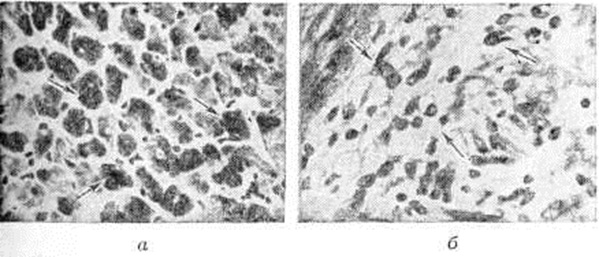

При экспериментальном Миокардит установлены нарушения окислительно-восстановительных и энергетических процессов в миокарде. Метаболические нарушения сопровождаются очаговыми и диффузными морфологический реакциями, которые дают возможность выделить паренхиматозный, воспалительно-инфильтративный, некротический, гигантоклеточный и смешанный варианты экспериментального Миокардит Наряду с очаговым кардиомиоцитолизом (рисунок 1, а), отёком и лимфогистиоцитарными инфильтратами в интерстиции (рисунок 1, б) наблюдается выраженная реакция антиген—антитело и с помощью меток выявляются В-лимфоциты и фиксированные антитела. Подострый и хронический варианты экспериментального Миокардит морфологически характеризуются мозаичностью и сочетанием воспалительных изменений с атрофией, гипертрофией и склерозом в миокарде. В эксперименте показана обратимость острого и подострого вариантов Миокардит, особенно под влиянием экспериментальной фармакотерапии. На моделях экспериментального Миокардит апробирован ряд средств, оказавшихся эффективными для лечения Миокардит у людей: противовирусные препараты (интерферон, кутизон, ремантадин), антибиотики, вакцины и сыворотки (противодифтерийная, противоменингококковая, противогриппозная), иммуно депрессоры (имуран), ненаркотические анальгетики (бруфен, индометацин), гипосенсибилизирующие и противовоспалительные препараты, анаболические средства.

Гистологический картина Миокардит отражает особенности его природы и стадию процесса. Систематизация по преобладающим гистологический проявлениям позволяет выделить 5 вариантов Миокардит: паренхиматозный, дистрофический, обозначавшийся как аллергическая дистрофия миокарда; воспалительно-инфильтративный; некротический, или деструктивный; гигантоклеточный; смешанный (цветной рисунок 4, 5, 6). В особую разновидность выделена так называемый васкулярная форма Миокардит, клинически проявляющаяся симптомами коронарной недостаточности, а морфологически — преобладанием картины васкулита (смотри полный свод знаний). С учётом относительной специфичности некоторых гисто л. изменений Миокардит подразделяют на 3 основные формы: неспецифический, гранулематозный (специфический) и гигантоклеточный Миокардит